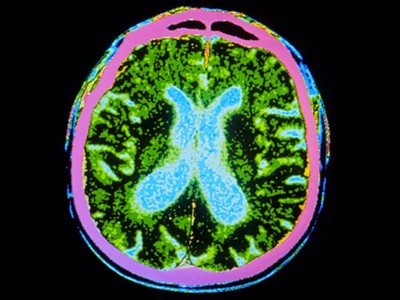

截至去年12月,共有83種源自多能干細胞的產品正在進行115項臨床試驗。帕金森病的治療方法比任何其他中樞神經系統疾病的治療方法都處于更先進的發展階段。帕金森病的特征是釋放神經遞質分子多巴胺的神經元逐漸喪失。帕金森病相關的運動癥狀,例如肌肉僵硬、運動遲緩、震顫和步態障礙,都是由中腦黑質區域神經元的耗竭引起的。

帕金森病是由于大腦中釋放多巴胺(多巴胺能)神經元逐漸喪失所致。Sawamoto 等人1和 Tabar 等人2進行了一項基于干細胞治療的臨床試驗。兩個團隊都使用了臨床級多能干細胞來補充多巴胺能神經元,這種細胞可以無限分裂并分化為任何細胞類型。Sawamoto等人使用了源自健康成年捐贈者細胞的誘導多能干細胞系,而Tabar等人使用了源自早期胚胎的人類胚胎干細胞系。干細胞經過培養,形成多巴胺能神經元祖細胞。這些細胞被移植到稱為殼核的大腦區域,殼核與尾狀核一起形成紋狀體。紋狀體與黑質相連,而黑質是多巴胺能神經元損失最為嚴重的部位。早期(I/II期)臨床試驗主要證實了該療法的安全性,同時也表明其在改善癥狀方面具有一定有效性。